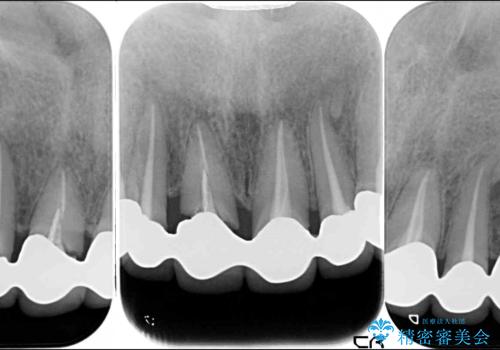

6歯全てが連結されていたため、外れかけていた右の犬歯は知らぬ間に虫歯が深くにまで進行していました。

深い虫歯の犬歯は、根管治療を行った後に部分矯正を行い、歯周外科処置により環境を整えてから、6歯それぞれのオールセラミッククラウンにて補綴することとしました。